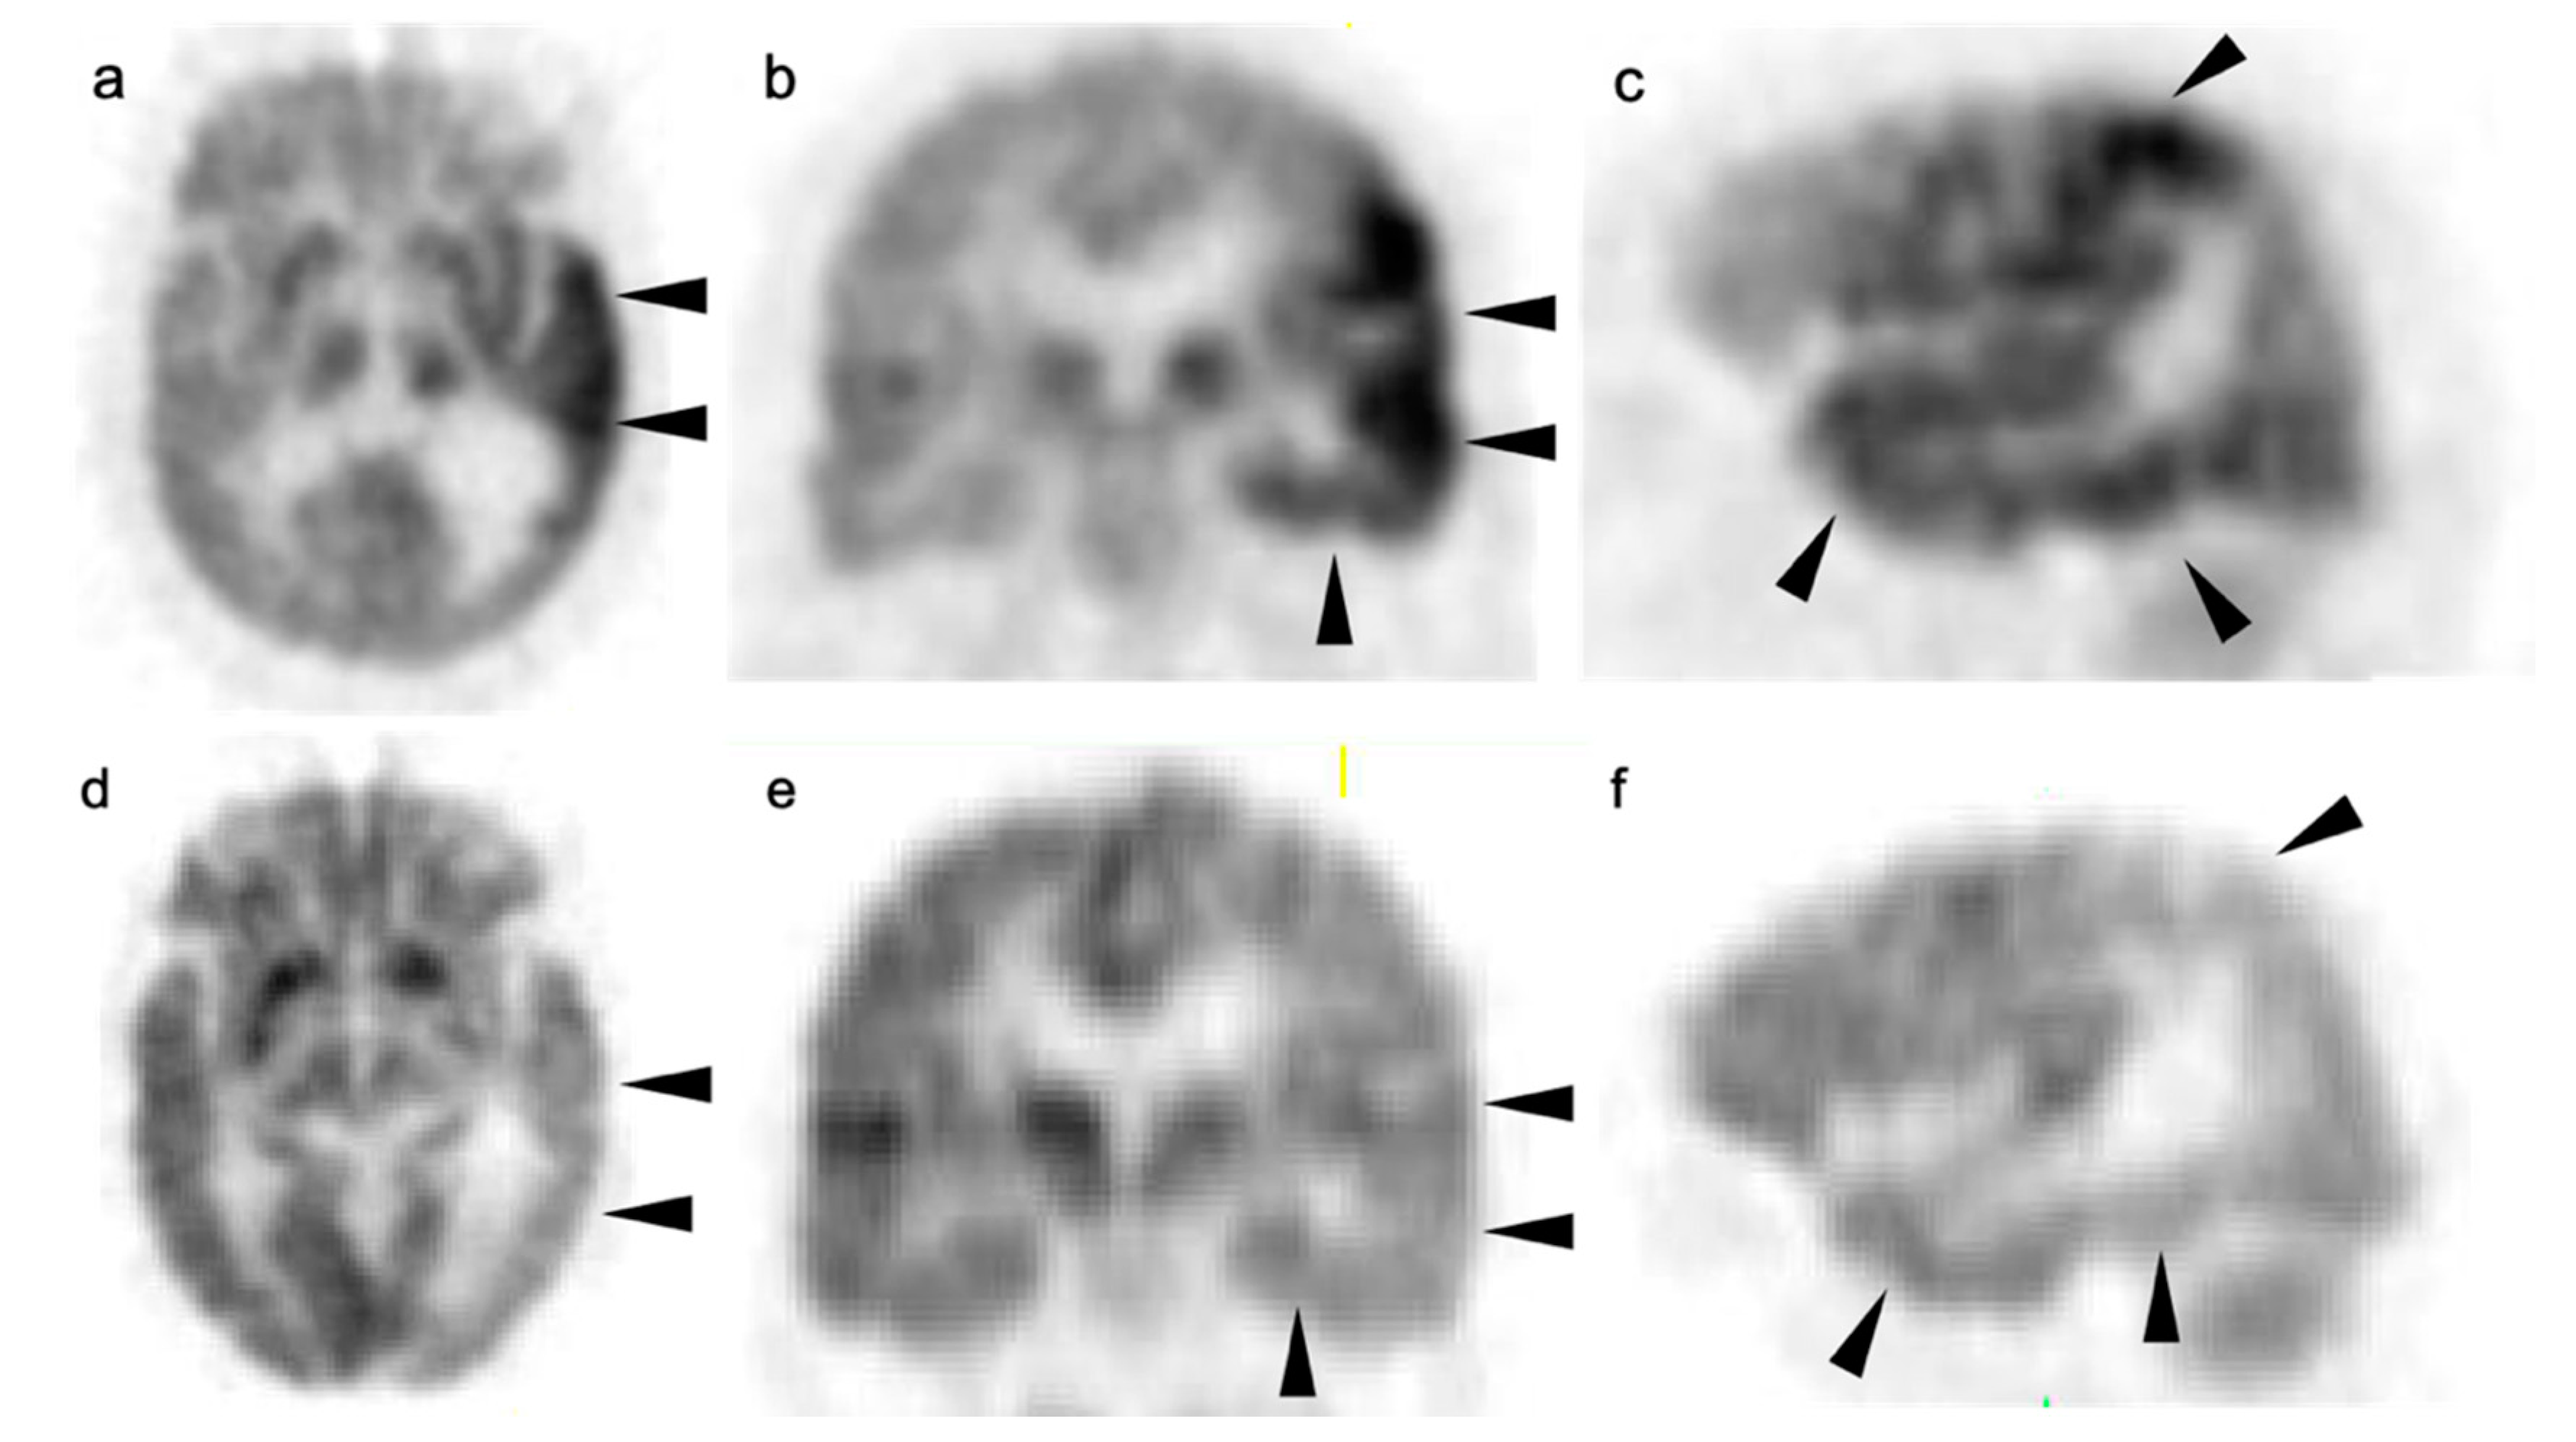

3. Neuro Oncology

3.3. Primary Brain Tumors

3.4. CNS Lymphoma

3.5. Brain Metastases

3.6. Response to Therapy